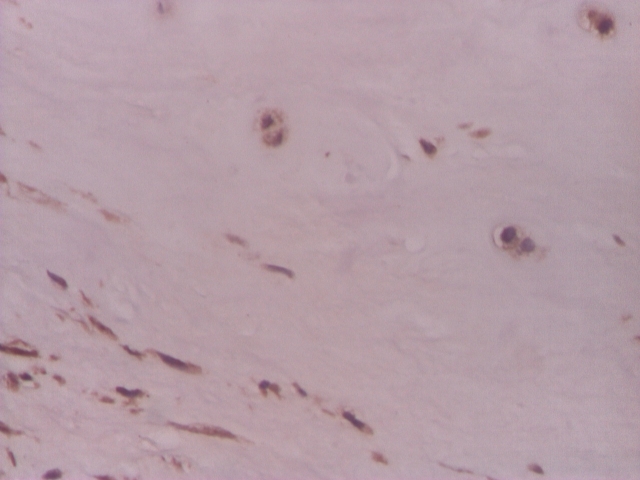

Figure 3.

Intervertebral disc, VEGF positive in rare chondrocyte–like cells and in fibroblast–like cells–IHC 200x

Figure 4.

Intervertebral disc, VEGF relatively rare in chondrocyte–like and fibroblast–like cells – IHC 200x